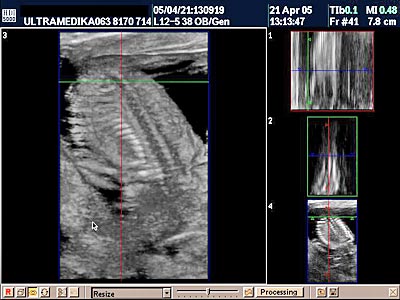

C) Pregled kičme ploda

Osnovna anatomija pršljenskih tela se ogleda u proceni epifiznih jezgara pršljenskih tela i deo je UZ dijagnostike u ovoj starosti trudnoće.